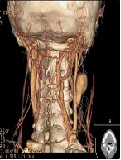

A Report of Right Carotid Artery Pseudoaneurysm with Pulmonary Artery Aneurysm

Quan Chen, Qibing Niu*, Shiqi Wen, Anqiang Li